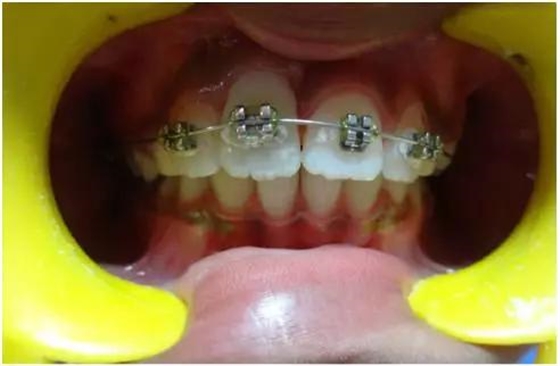

正畸牽引5周后,牙齒復(fù)位到其原始位置,與其他切牙完全對(duì)齊(圖3)。開(kāi)始嘗試血運(yùn)重建。重新打開(kāi)根管,使用次氯酸鈉和生理鹽水沖洗。然后插入無(wú)菌根管銼,并將其推到根尖處,以使血流進(jìn)入根管。一旦血液到達(dá)釉牙骨質(zhì)界,放置一個(gè)濕潤(rùn)的無(wú)菌棉球靜置15分鐘,直到血凝塊形成,再放置約2-3mm的MAT在血凝塊上。在MAT上覆蓋一個(gè)濕棉球,隨后進(jìn)行臨時(shí)修復(fù)。以后再替換為玻璃離子水門(mén)汀墊底和復(fù)合樹(shù)脂修復(fù)。復(fù)診時(shí)間為1、3、6、9和12月。正畸復(fù)位保留12周。然而,在這么長(zhǎng)的保留期內(nèi)還是復(fù)發(fā)了錯(cuò)位,這也強(qiáng)調(diào)了在嚴(yán)重侵入的情況下長(zhǎng)期復(fù)位的重要性,因?yàn)槔奂暗难例X周圍出現(xiàn)大量的牙槽骨喪失(圖 4)。

牙齦: 即使病人保持良好的口腔衛(wèi)生,在正畸治療完成后,在受累的牙齒上能觀察到明顯的牙齦萎縮。系帶附著位置可能是原因之一。修整系帶可能可以解決這個(gè)問(wèn)題(圖4)。在軟組織愈合后,復(fù)發(fā)的牙齒復(fù)位至正常位置(圖 5)。經(jīng)過(guò)6周病人細(xì)致的口腔衛(wèi)生維護(hù),牙齦狀況和美觀得到改善(圖6和7)。